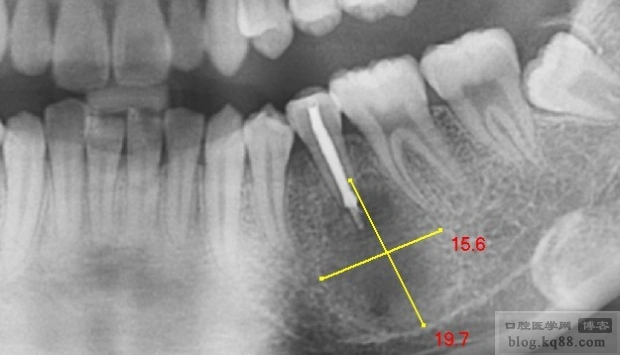

根尖囊肿

巨型根尖囊肿